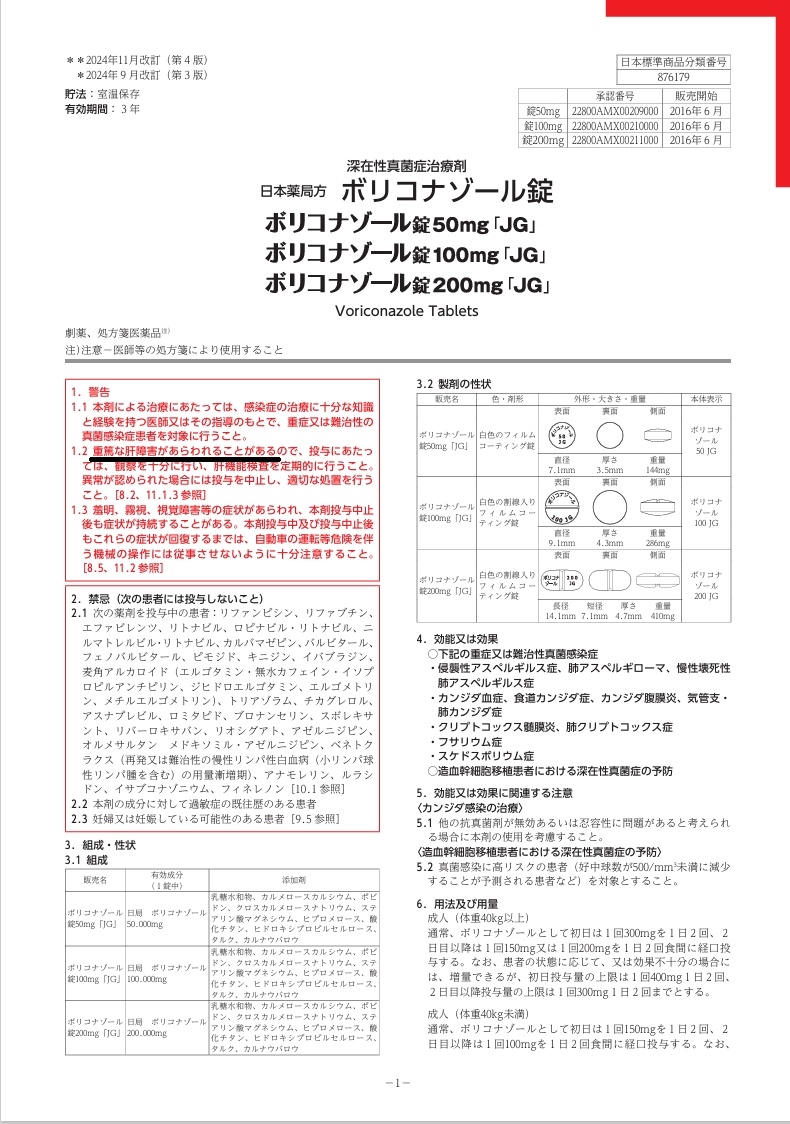

ボリコナゾールは、侵襲性肺アスペルギルス症・アスペルギルス甲状腺炎、カンジダ血症/食道カンジダ症、クリプトコックス髄膜炎/肺クリプトコックスなど深在性真菌症(カビ)の治療薬です。

重篤(重症)な肝障害は有名ですが、副腎皮質機能不全、甲状腺機能亢進症、甲状腺機能低下症(頻度不明)、SIADH(抗利尿ホルモン不適合分泌症候群)(1~5%未満)も引き起こします(添付文書より)。